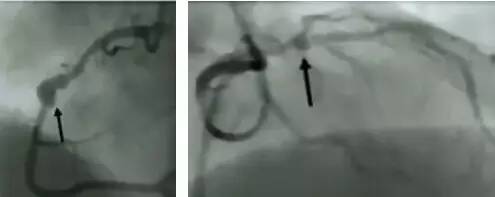

0级:无血栓;1级:管腔显影模糊;2级:有明确血栓,但<1/2血管直径;3级:血栓为1/2~2倍血管直径;4级:血栓≧2倍血管直径;5级:血栓完全堵塞血管。

图5 冠脉血栓4级(左)和5级(右)